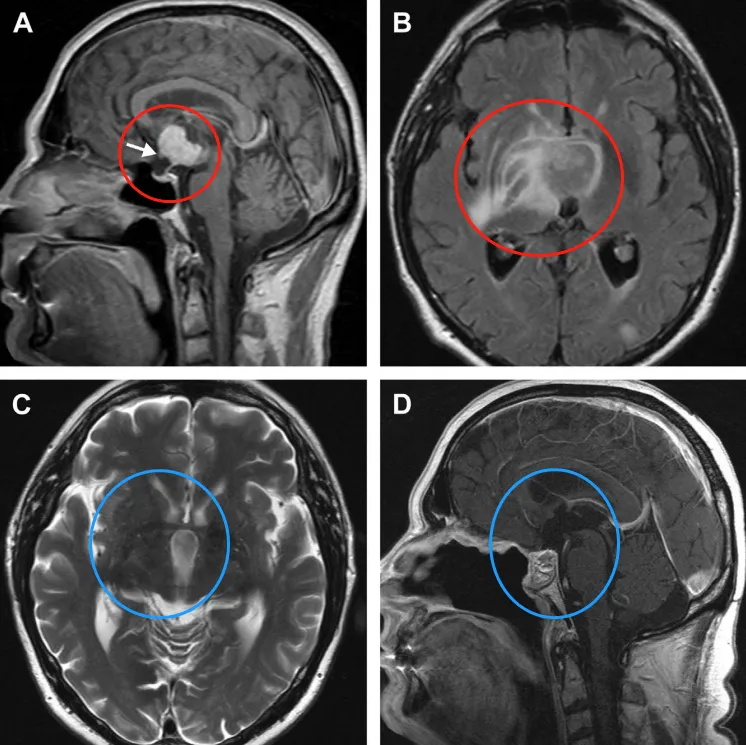

图14。鞍上增强MRI显示,肿瘤延伸至三脑室,有实性成分(a)。视神经交叉向前移位(箭头)。垂体和蝶鞍似乎正常。由于T2病灶周围水肿和反转恢复图像液体衰减并右侧基底神经节外侧延伸,怀疑下丘脑侵犯(B)。施罗德教授在内镜下行全切术,包括已被肿瘤浸润损害的部分垂体柄。术后2年MRI未见肿瘤复发(C,D)。水肿完全消退(C)。图像(D)也显示鼻中隔皮瓣重建颅底。

点击阅读完整案例:国际内镜主席Schroeder图文详解,如何内镜手术切除颅咽管瘤?